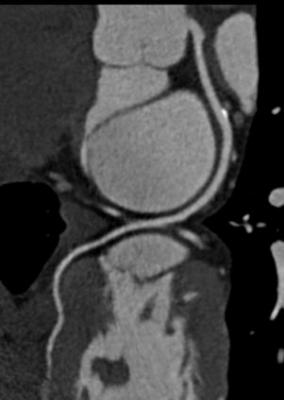

View Calcium Score Cardiac Ct Scan Images. The scan result did not influence the decision to perform angiography. A coronary ct calcium scan is a computed tomography (ct) scan of the heart for the assessment of severity of coronary artery disease.

Another name for this test is coronary artery calcium scoring. Background coronary artery calcium scoring uses cardiac ct, a noninvasive, radiographic technique, to detect calcium deposits in coronary arteries. This is not the stuff you get on your teeth, but a different kind found in your arteries.

The calcium that the scan is looking for is part of plaque. Overall sensitivity was 99%, and specificity was 28% for the presence of any. Our cardiac ct essentials course was designed and delivered by ct guru, dr ronak rajani. Cardiac ct for calcium scoring.